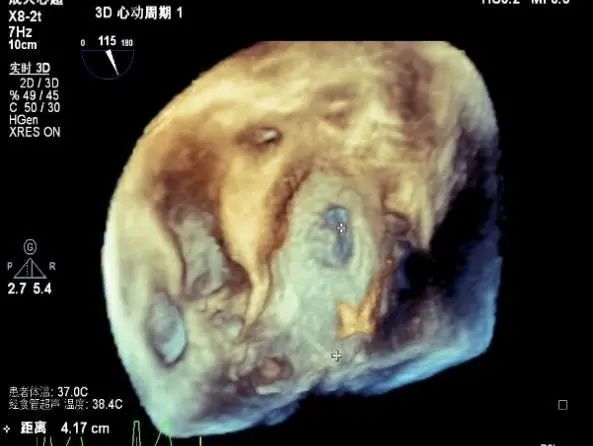

3D MV View:P1区瓣体瘤形成并中央型破裂孔,脱垂从P1到P2区,脱垂宽度13.1mm,破裂孔大小4.1×5.6mm

TEE Bicom view:主要病变区域为P1区,瓣叶中部可见连续性中断